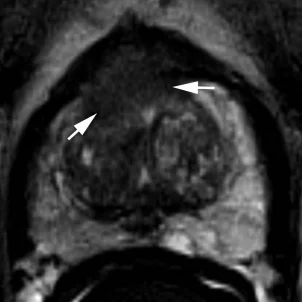

Нет раннего накопления контрастного препарата, или диффузное мультифокальное накопление, не соответствующее очагу на Т2 и DWI

Раннее накопление контрастного препарата (раньше или одновременно с нормальной тканью железы), соответствует очагу на Т2 и DWI